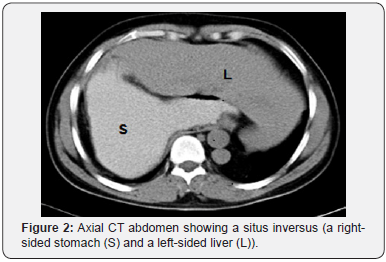

His general investigations (full blood count, random blood glucose, renal and liver profiles) were within normal ranges. His CXR showed normal lungs, levocardia and a right-sided gastric bubble. ECG revealed no abnormalities. A trans-thoracic echocardiography was normal apart from unusual drainage of hepatic veins directly into the right atrium. A multi-detector CT (MDCT) scan of the abdomen (with oral and intravenous contrast) confirmed the hiatus hernia (Figure 1) and revealed a right-sided stomach, a two-humped left-sided liver (Figure 2), polysplenia (three splenic masses, two on the left beneath the liver and one on the right) (Figure 3), a pre-pancreatic portal vein (Figure 4) and an absent inferior vena cava (IVC) with a direct continuation of azygous and hemi-azygous veins (Figure 5). Therefore, CT findings were consistent with heterotaxy syndrome with a left isomerism (polysplenia syndrome).